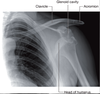

Review this radiograph of the shoulder.

A